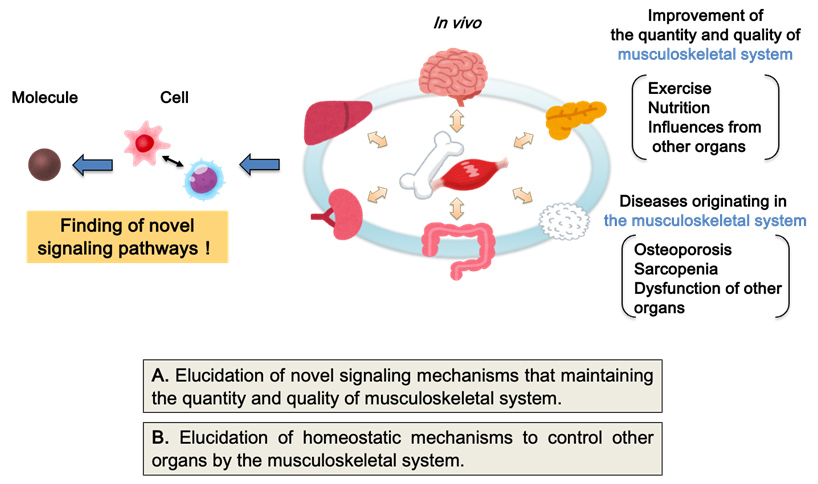

(1) Elucidation of novel homeostatic maintenance mechanisms centered on the musculoskeletal system

Bone and skeletal muscle secrete hormones that regulate the functions of other organs, implying that musculoskeletal disorders impact not only the risk of immobility but also systemic homeostasis and lifespan. Consequently, we are advancing two primary research projects, aiming to uncover pathophysiological mechanisms beyond existing concepts and to foster the development of novel preventive and therapeutic strategies.

A. Elucidation of novel signaling mechanisms maintaining the quantity and quality of musculoskeletal systems

Remodeling (reconstruction: repetition of synthesis (formation) and degradation (absorption)) of bone and skeletal muscle includes steady-state remodeling and remodeling after injury such as fracture or muscle damage. In order to discover novel factors involved in bone and skeletal muscle homeostasis, we have created various mouse models of remodeling at different stages, and are conducting comprehensive gene expression and protein analysis. Currently, we are discovering new regulatory mechanisms of blood vessels and nerves in bone marrow by osteoblasts and of skeletal muscle regeneration by immune cells. We will continue to elucidate new mechanisms of musculoskeletal homeostasis that lead to healthy longevity.

B. Elucidation of homeostatic mechanisms to control other organs by the musculoskeletal system